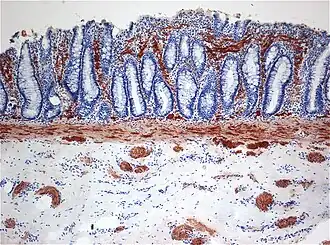

![]() Гистопатология болезни Гиршпрунга | |